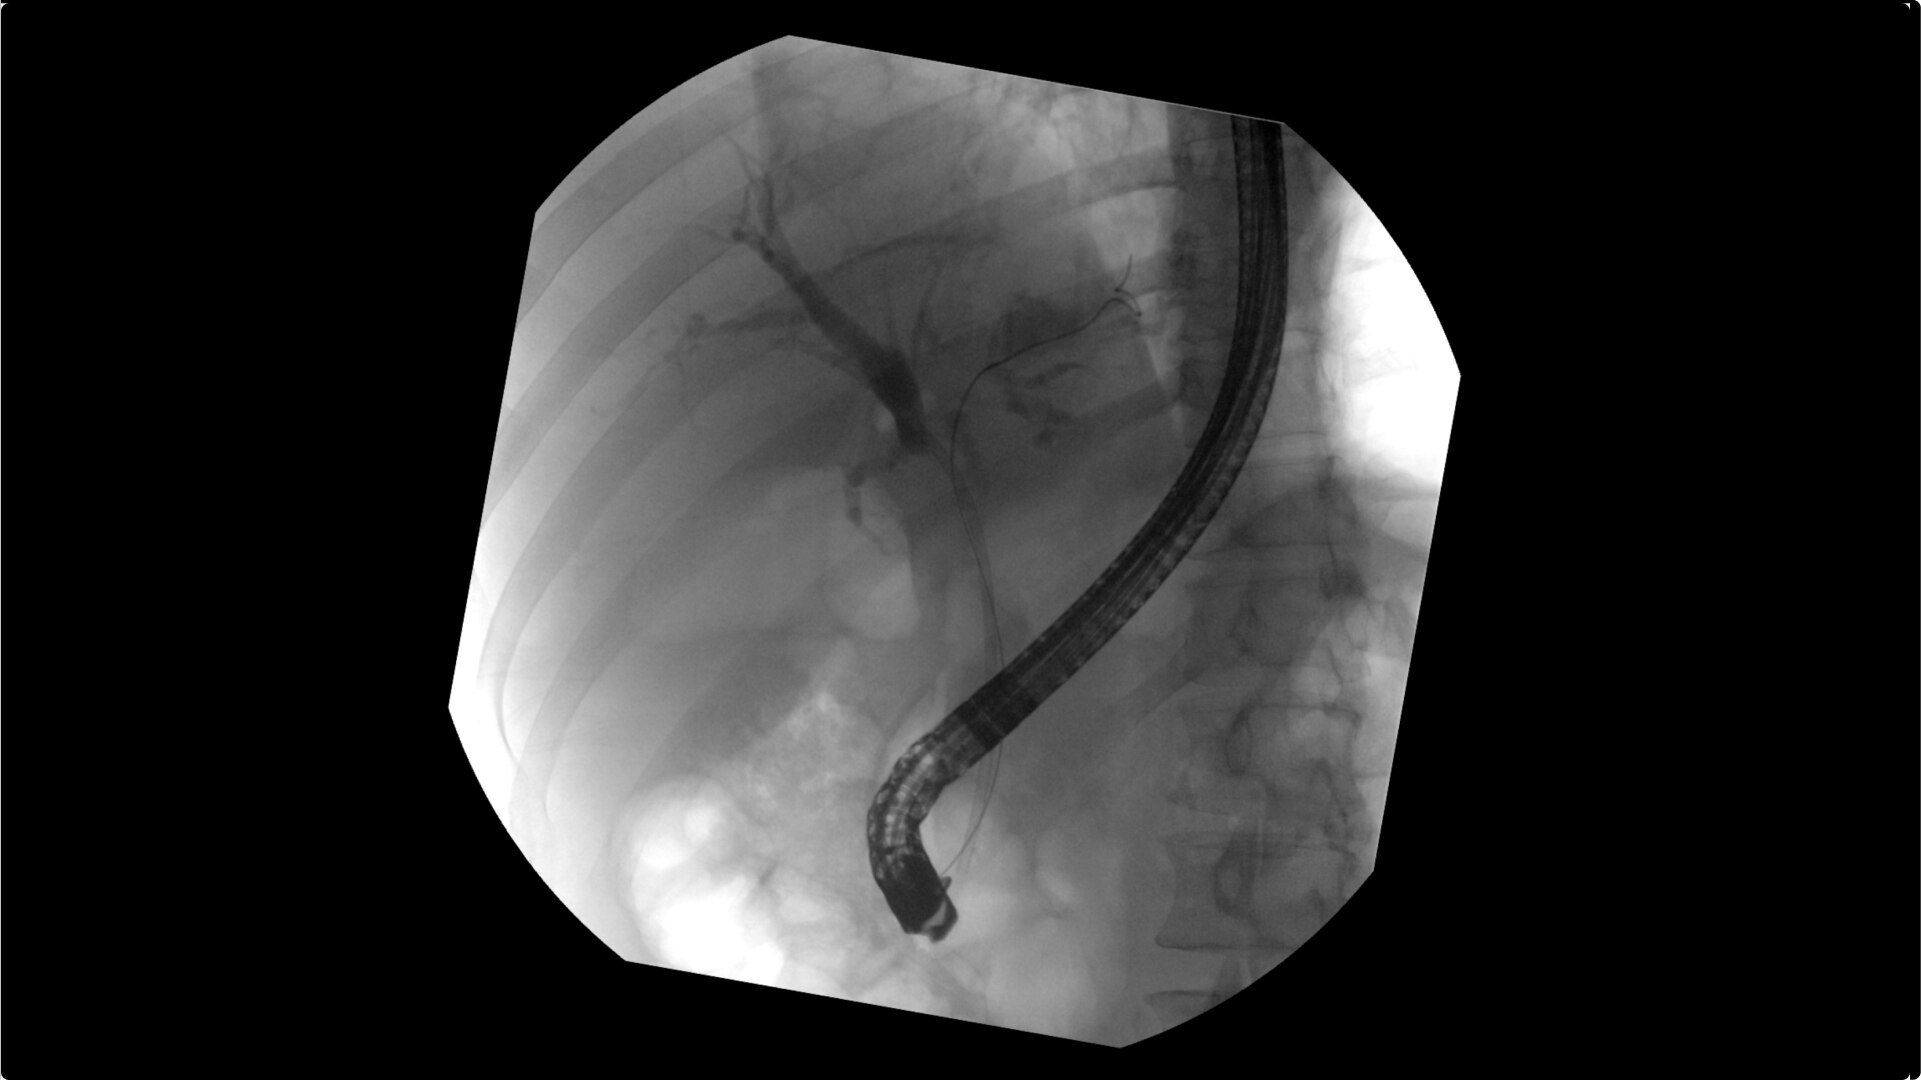

Clearly visualize the GI tract of patients, regardless of size, during a wide range of endoscopic procedures, including ERCP. OEC C-arms offer amazing image quality at low dose and provide enhancements for clear visualization during movement in soft tissue, such as during guidance of low-density drainage tubes or thin biopsy brushes. A large, clear display with comfortable viewing enables effortless workflow.

Live Zoom up to 4X during a fluoro or Cine without the additional dose of Mag modes or resulting X-ray tube heat buildup to see guidewires or tubes during procedures.

Capture up to 22% more Field of View by positioning the OEC Elite detector closer to patient anatomy with the OEC low-profile X-ray tube housing compared to mono-block C-arms.

Complex gastrointestinal procedures require powerful imaging systems. OEC premium C-arms perform in a variety of procedures such as:

• Endoscopic retrograde cholangiopancreatography